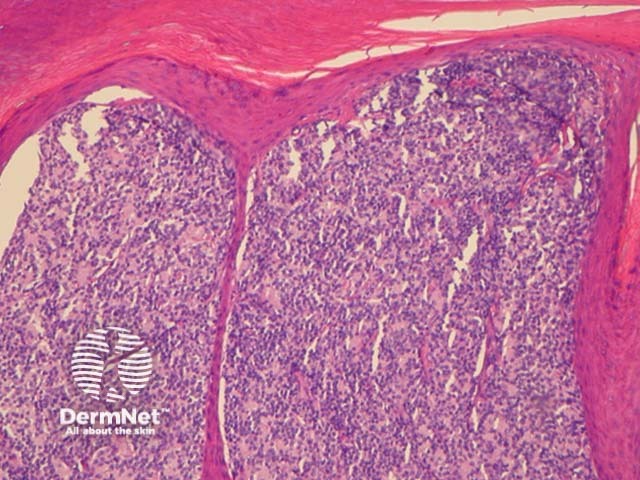

Histologically, indolent CD8+ lymphoid proliferations are characterised by a dense dermal infiltrate of non-epidermotropic, medium sized pleomorphic lymphocytes. These form a dense mass in the dermis and may involve subcutaneous tissues (figures 1-5).